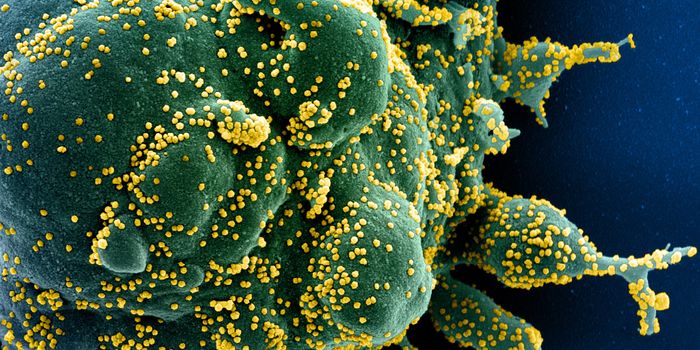

MAR 14, 2022ImmunologyThough it may happen at different rates for different microbes, mutations happen, and SARS-CoV-2, the virus that causes ...

NOV 26, 2021MicrobiologyOn Thursday, November 2021, South African health officials announced that they had identified a new variant of the pande ...

MAY 10, 2021MicrobiologyThe pandemic virus SARS-CoV-2 has changed the world in devastating ways, taking hundreds of thousands of lives & new var ...